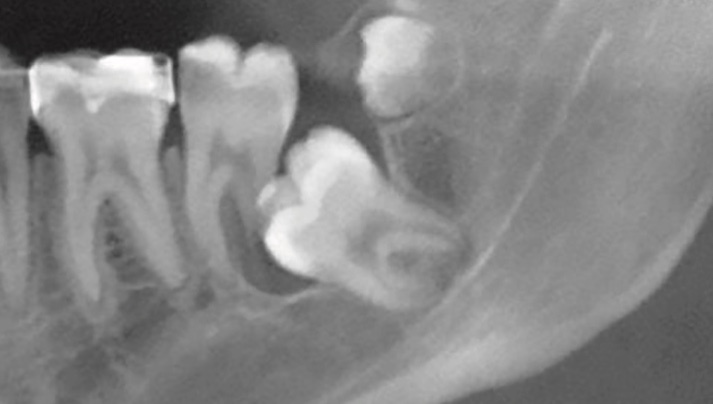

La gingivitis es la inflamación de las encías debido a la acumulación del sarro entre diente y encía provocando la inflamación de las mismas y el sangrado. Si la enfermedad no se resuelve a tiempo y la infección sigue su evolución puede derivar en una periodontitis. En esta fase las encías se retraen y puede dañar el hueso que soporta el diente y favorecer su pérdida.